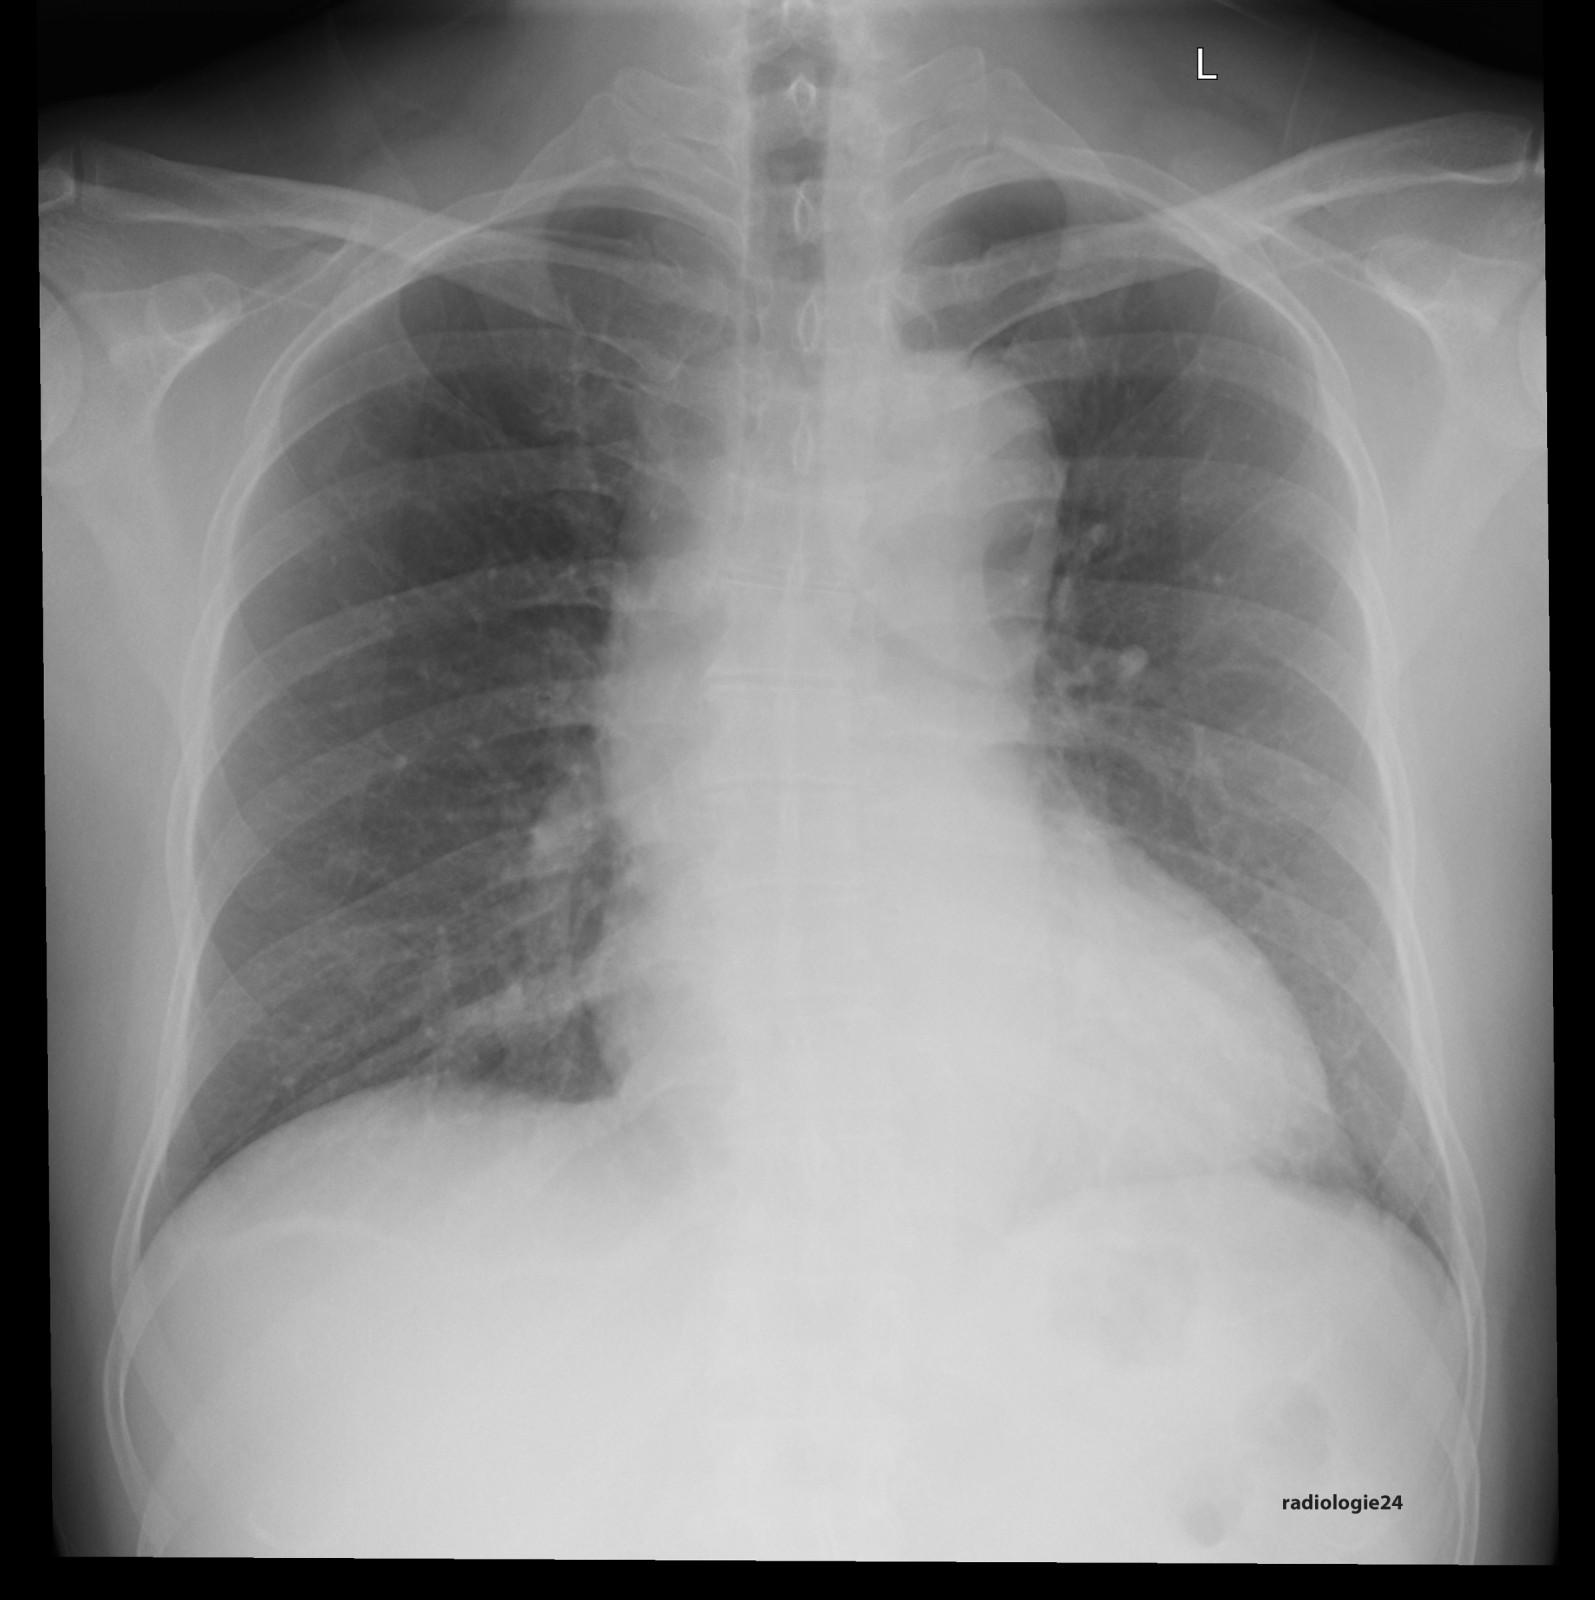

Röntgenfall des Monats Oktober 2017 mit Auflösung

48 jähriger Patient. Klinische Angaben: Thoraxschmerzen, afebril, hypertensiv entgleist. Fragestellung: Infektzeichen? Kardiale Kompensation? Diagnose? Weitere radiologische Diagnostik?